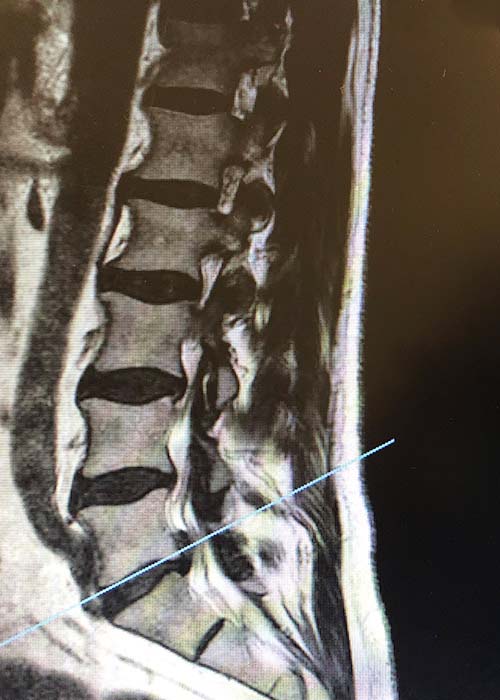

En primer lugar, y con el fin de conocer con exactitud el nivel de gravedad ante el que nos encontrábamos, se realizó una valoración de los síntomas que presentaba el paciente y la complementamos junto a una serie de radiografías.

radiografia-hermia-discal-L5S1